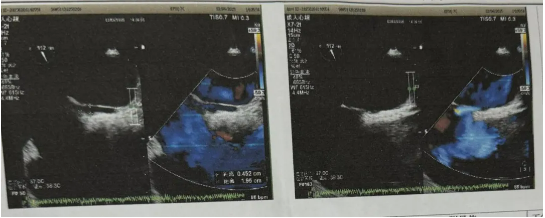

男性患者,35歲,長(zhǎng)期受不明原因偏頭痛困擾,伴頭暈、眼花,發(fā)作起來疼痛難忍,影響行動(dòng),期間就診神內(nèi)科、耳鼻喉科等,頭顱、頸椎等檢查均無異常。近日,頭痛癥狀發(fā)作頻繁、藥物緩解效果甚微,為明確病因?qū)で笾委?,患者來我院就診,行經(jīng)顱多普勒檢查,結(jié)果顯示Valsava動(dòng)作后出現(xiàn)大量、高強(qiáng)度栓子信號(hào)(呈雨簾狀),右心聲學(xué)造影結(jié)果也呈陽性,支持右向左分流,大量。進(jìn)一步的食道超聲檢查明確診斷:房間隔中段存在一長(zhǎng)約19.5mm、寬約4.5mm的斜形裂隙,確診為卵圓孔未閉(長(zhǎng)隧道型),符合介入封堵指征。

經(jīng)過術(shù)前精心準(zhǔn)備,手術(shù)順利開展,在超聲影像精準(zhǔn)引導(dǎo)下,心胸血管外科團(tuán)隊(duì)通過股靜脈穿刺建立介入通道,將可降解封堵器精準(zhǔn)釋放在卵圓孔裂隙處。術(shù)中實(shí)時(shí)超聲監(jiān)測(cè)顯示封堵器貼合緊密,分流消失,手術(shù)歷時(shí)僅40分鐘。術(shù)后患者頭痛癥狀顯著緩解,無需長(zhǎng)期服用抗凝藥物,第二天下床,第三天即出院,生活恢復(fù)正常。(供稿通訊員:凡兵、彭均偉、孫暉)